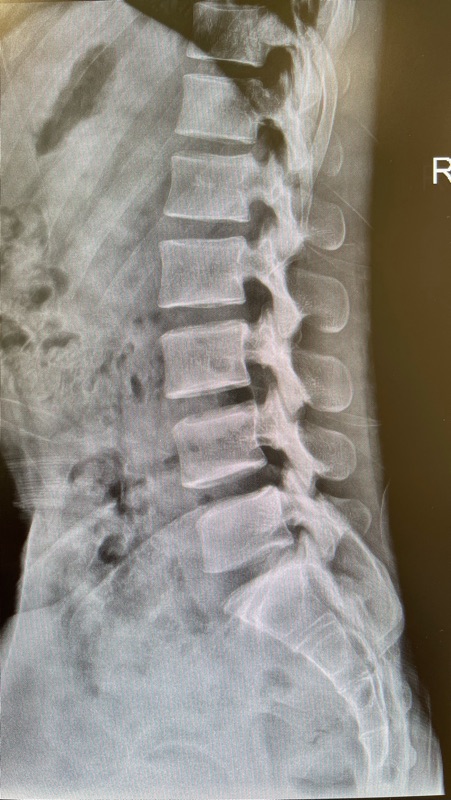

✔ 3) เอกซเรย์หลังส่วนเอว

ดูว่ามีข้อเสื่อม กระดูกงอก หรือกระดูกสันหลังเคลื่อนหรือไม่